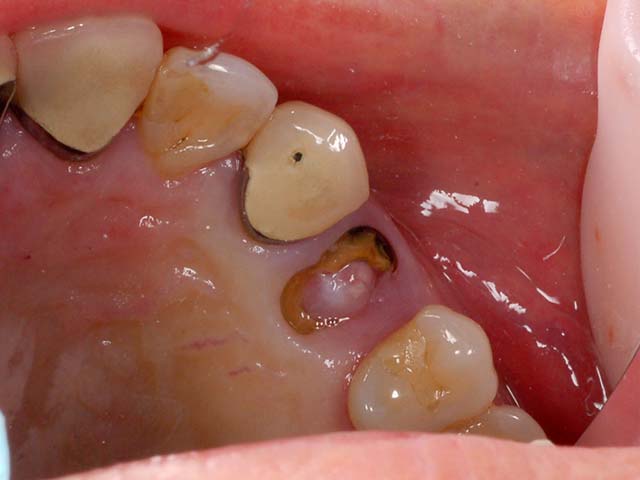

王小姐右上有一顆根管治療後的牙齒,不幸斷裂,經由電腦斷層評估,我們使用新技術,即拔即種,拔除右上第一小臼齒同時植入植體,降低患者手術疼痛感,與節省時間,經由四個月的等待牙齒終於裝置完成,回復正常咀嚼功能,與良好的美觀。